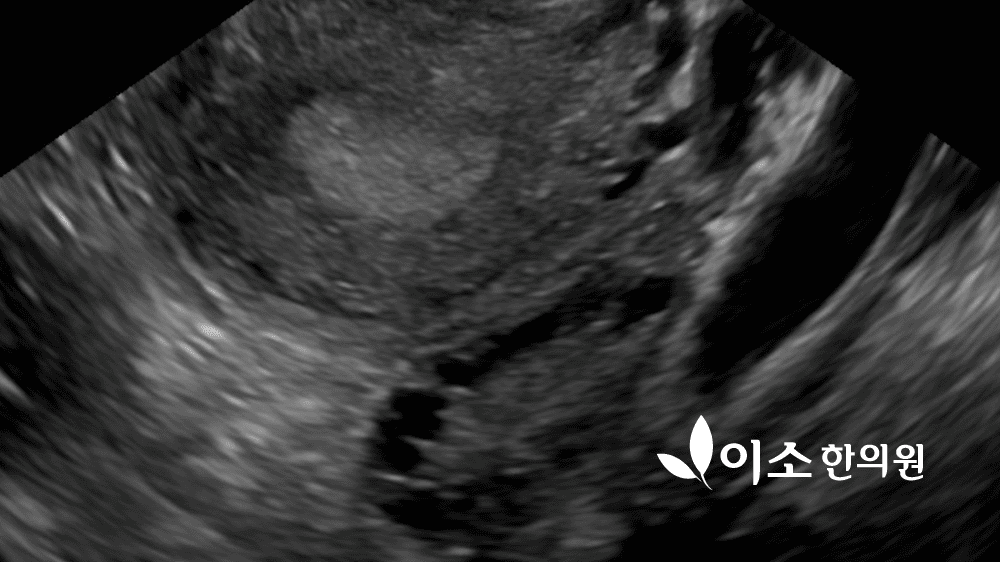

여드름 환자가 생리불순, 월경불순이 함께 있을 때 다낭성난소증후군을 가장 먼저 의심합니다. 여드름 환자가 생리불순이나 무월경, 혹은 생리 주기가 들쑥날쑥하거나 수개월씩 생리를 하지 않을 때, 산부인과에서 초음파로 다낭성 난소를 확인하고 진단받는 것이 일반적입니다.